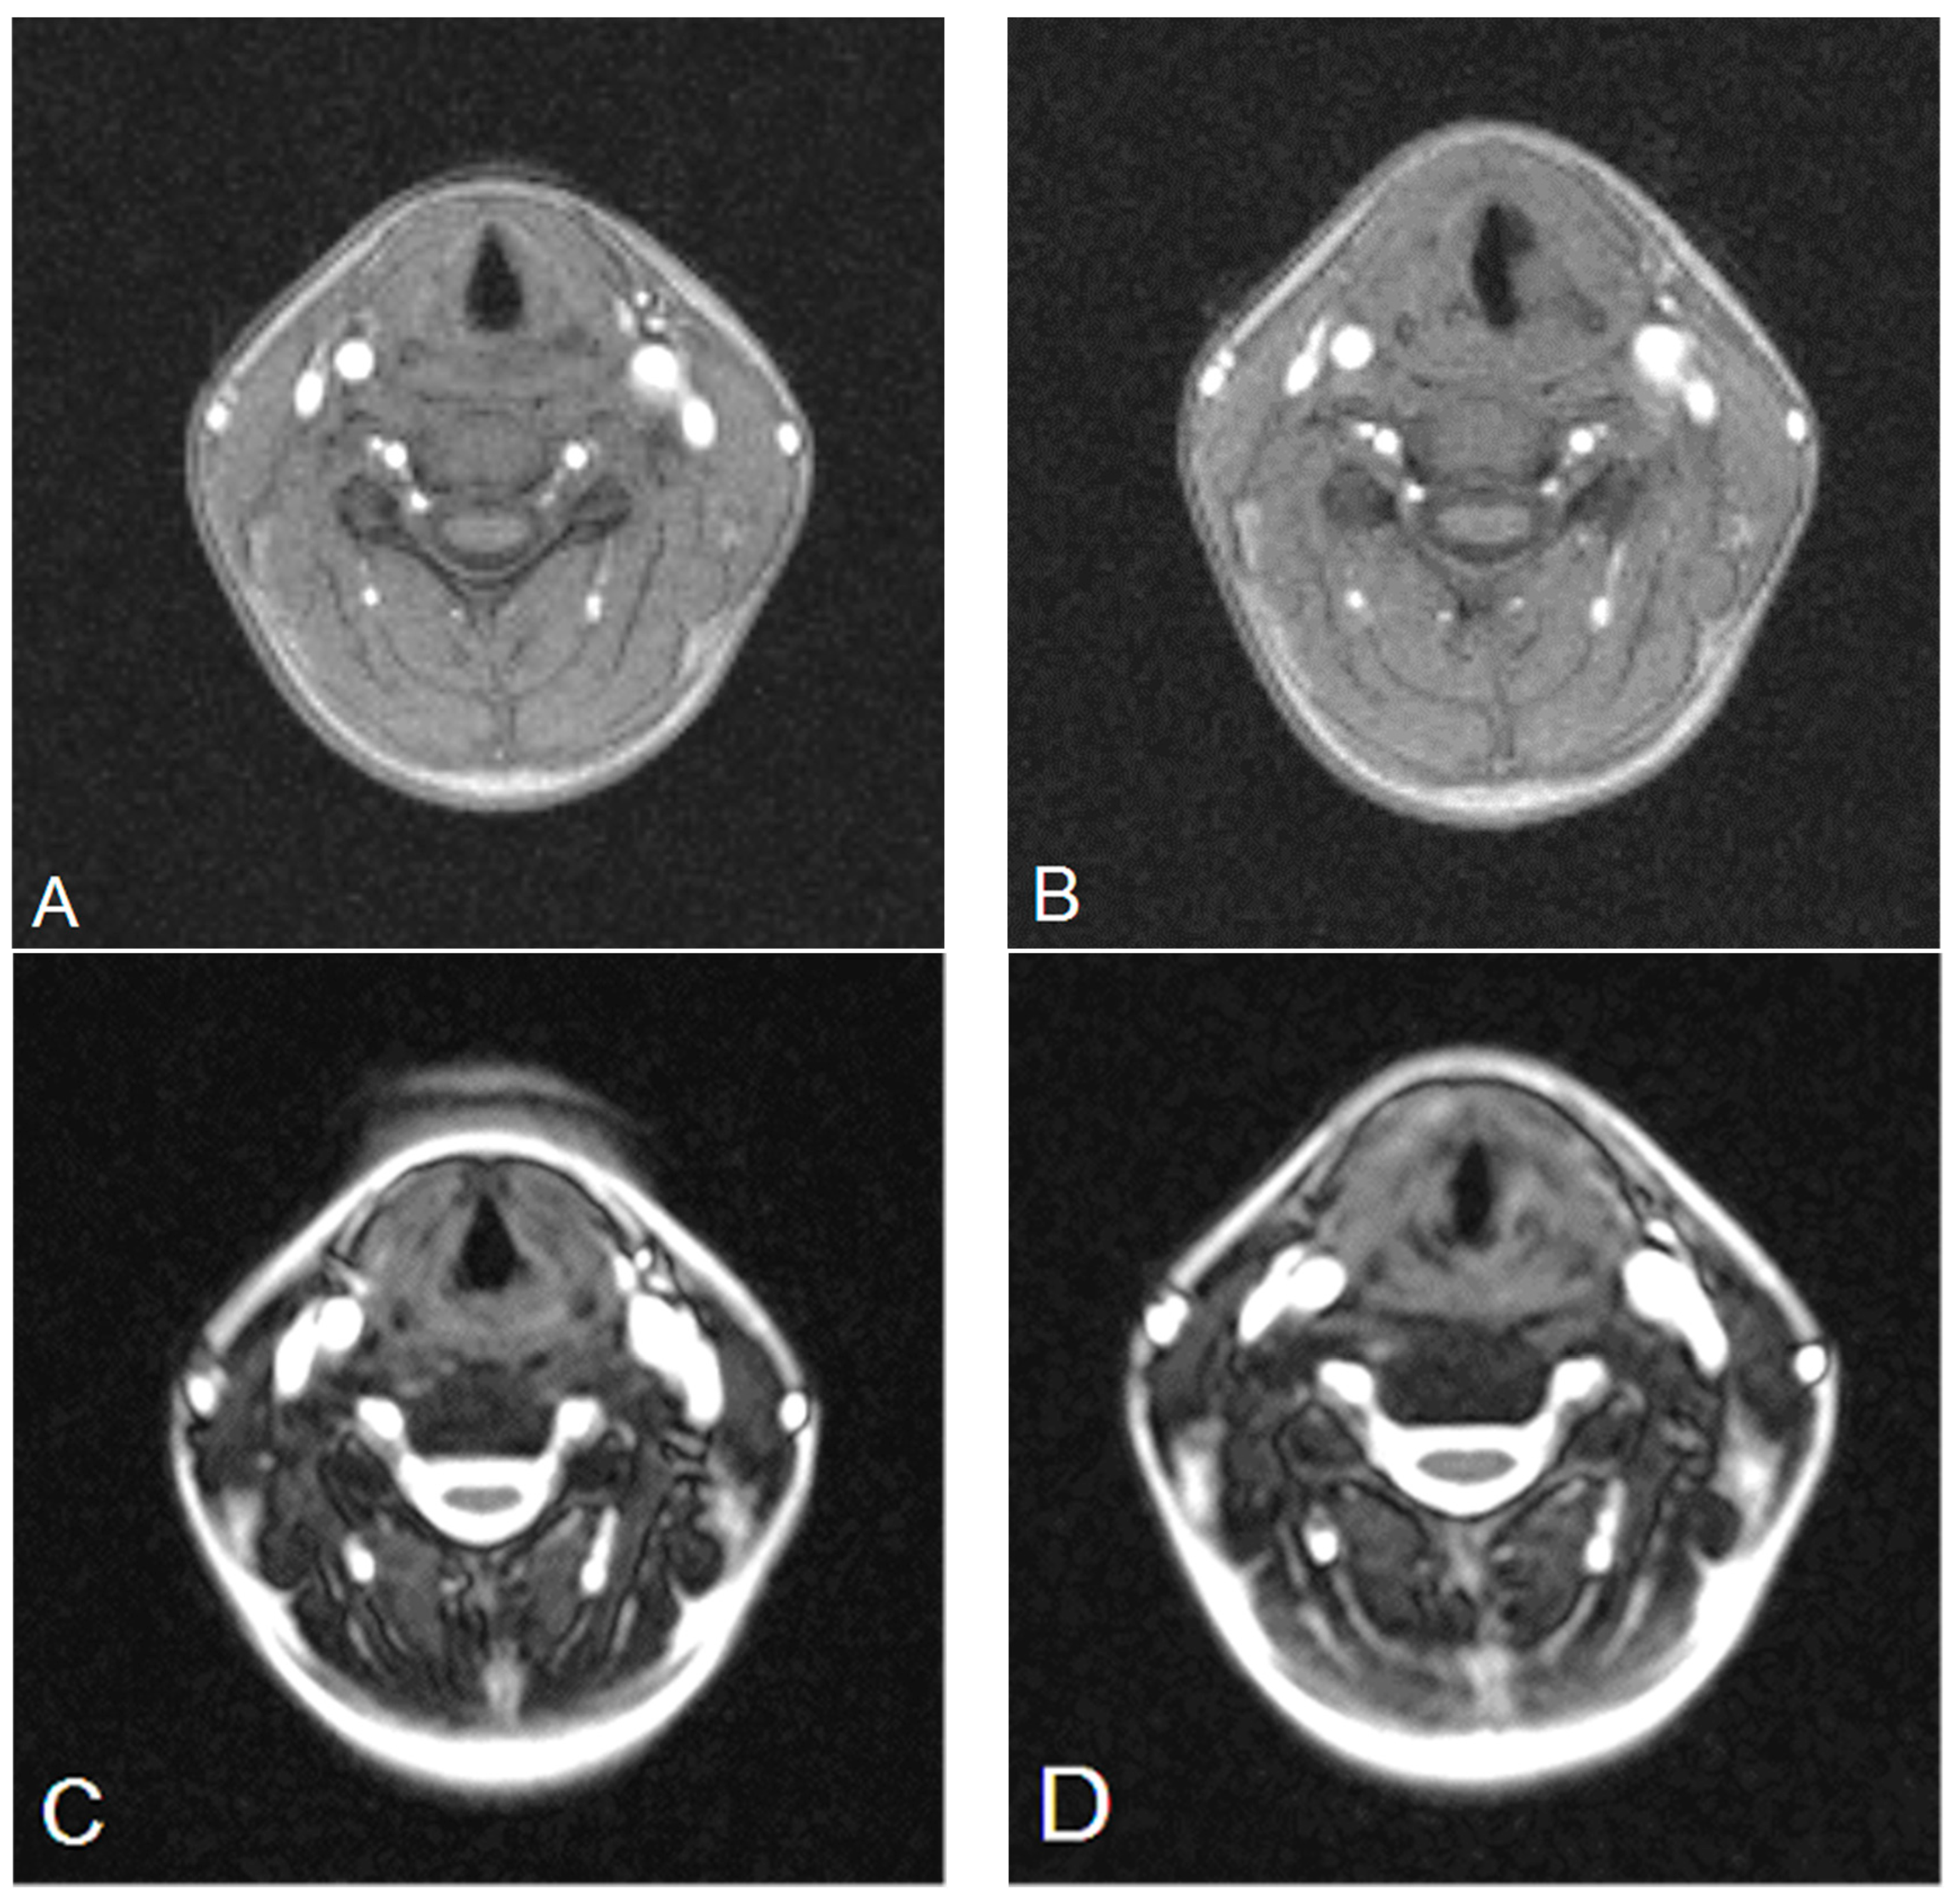

3.1. Analysis of the Qualitative Data Obtained during Ultrasound and MRI in Patients with Goiter Compared to Direct Laryngoscopy

3.2. Analysis of the Quantitative Data Obtained Using Ultrasound and MRI Methods (GRE and TRUFI Sequences) before and after Thyroidectomy